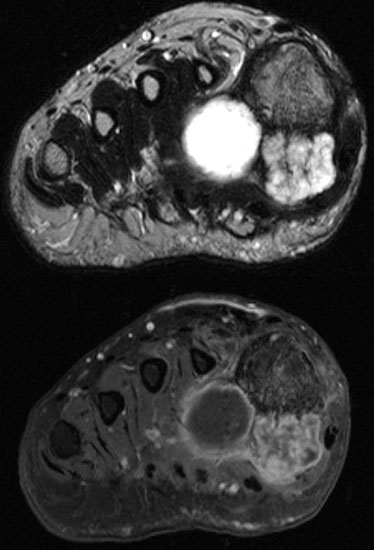

Die Magnetresonanztomographie erlaubt nicht nur die exakte Beurteilung der intramedul­lären und extraossären Tumorausdehnung einschließlich reaktiver Zone, sondern auch die genaue Lagebeziehung zu neurovaskulären Strukturen (Abb. 8) und eine Differenzierung zwischen vitalen versus nekrotischen Tumoranteilen. Dies ist insbesondere für eine mögliche Biopsie von entscheidender Bedeutung um repräsentatives Tumorgewebe für die histo­patho­logische Analyse gewinnen zu können. Die bei Verdacht auf einen Knochen- oder Weichteiltumor vom Radiologen durchzuführenden Standardprotokolle der MRT wurden im Jahr 2006 von der Arbeitsgemeinschaft Muskuloskelettale Diagnostik der Deutschen Röntgengesellschaft veröffentlicht (Tab.2) und gewähren bei entsprechender Umsetzung eine qualitativ hochwertige Untersuchung (DRG, 2006).

Je nach vermuteter Tumorentität können zusätzliche Sequenzen durchgeführt werden (z. B. Häm-Sequenzen bei pigmentierter villonodulärer Synovialitis). Bestimmte Tumorentitäten können alleine durch die MRT-Untersuchung aufgrund ihres typischen Signalverhaltens diagnostiziert werden 146. Aufgrund der Seltenheit und der großen Heterogenität muskulo-skelettaler Tumoren sind spezielle Fragestellungen zu diesem Thema aber auch für eine Vielzahl von Radiologen nicht alltäglich. Es empfiehlt sich deshalb, im Zweifelsfall die Zweitmeinung eines tumororthopädischen Zentrums einzuholen (Link für Online-Konsil im Anhang).